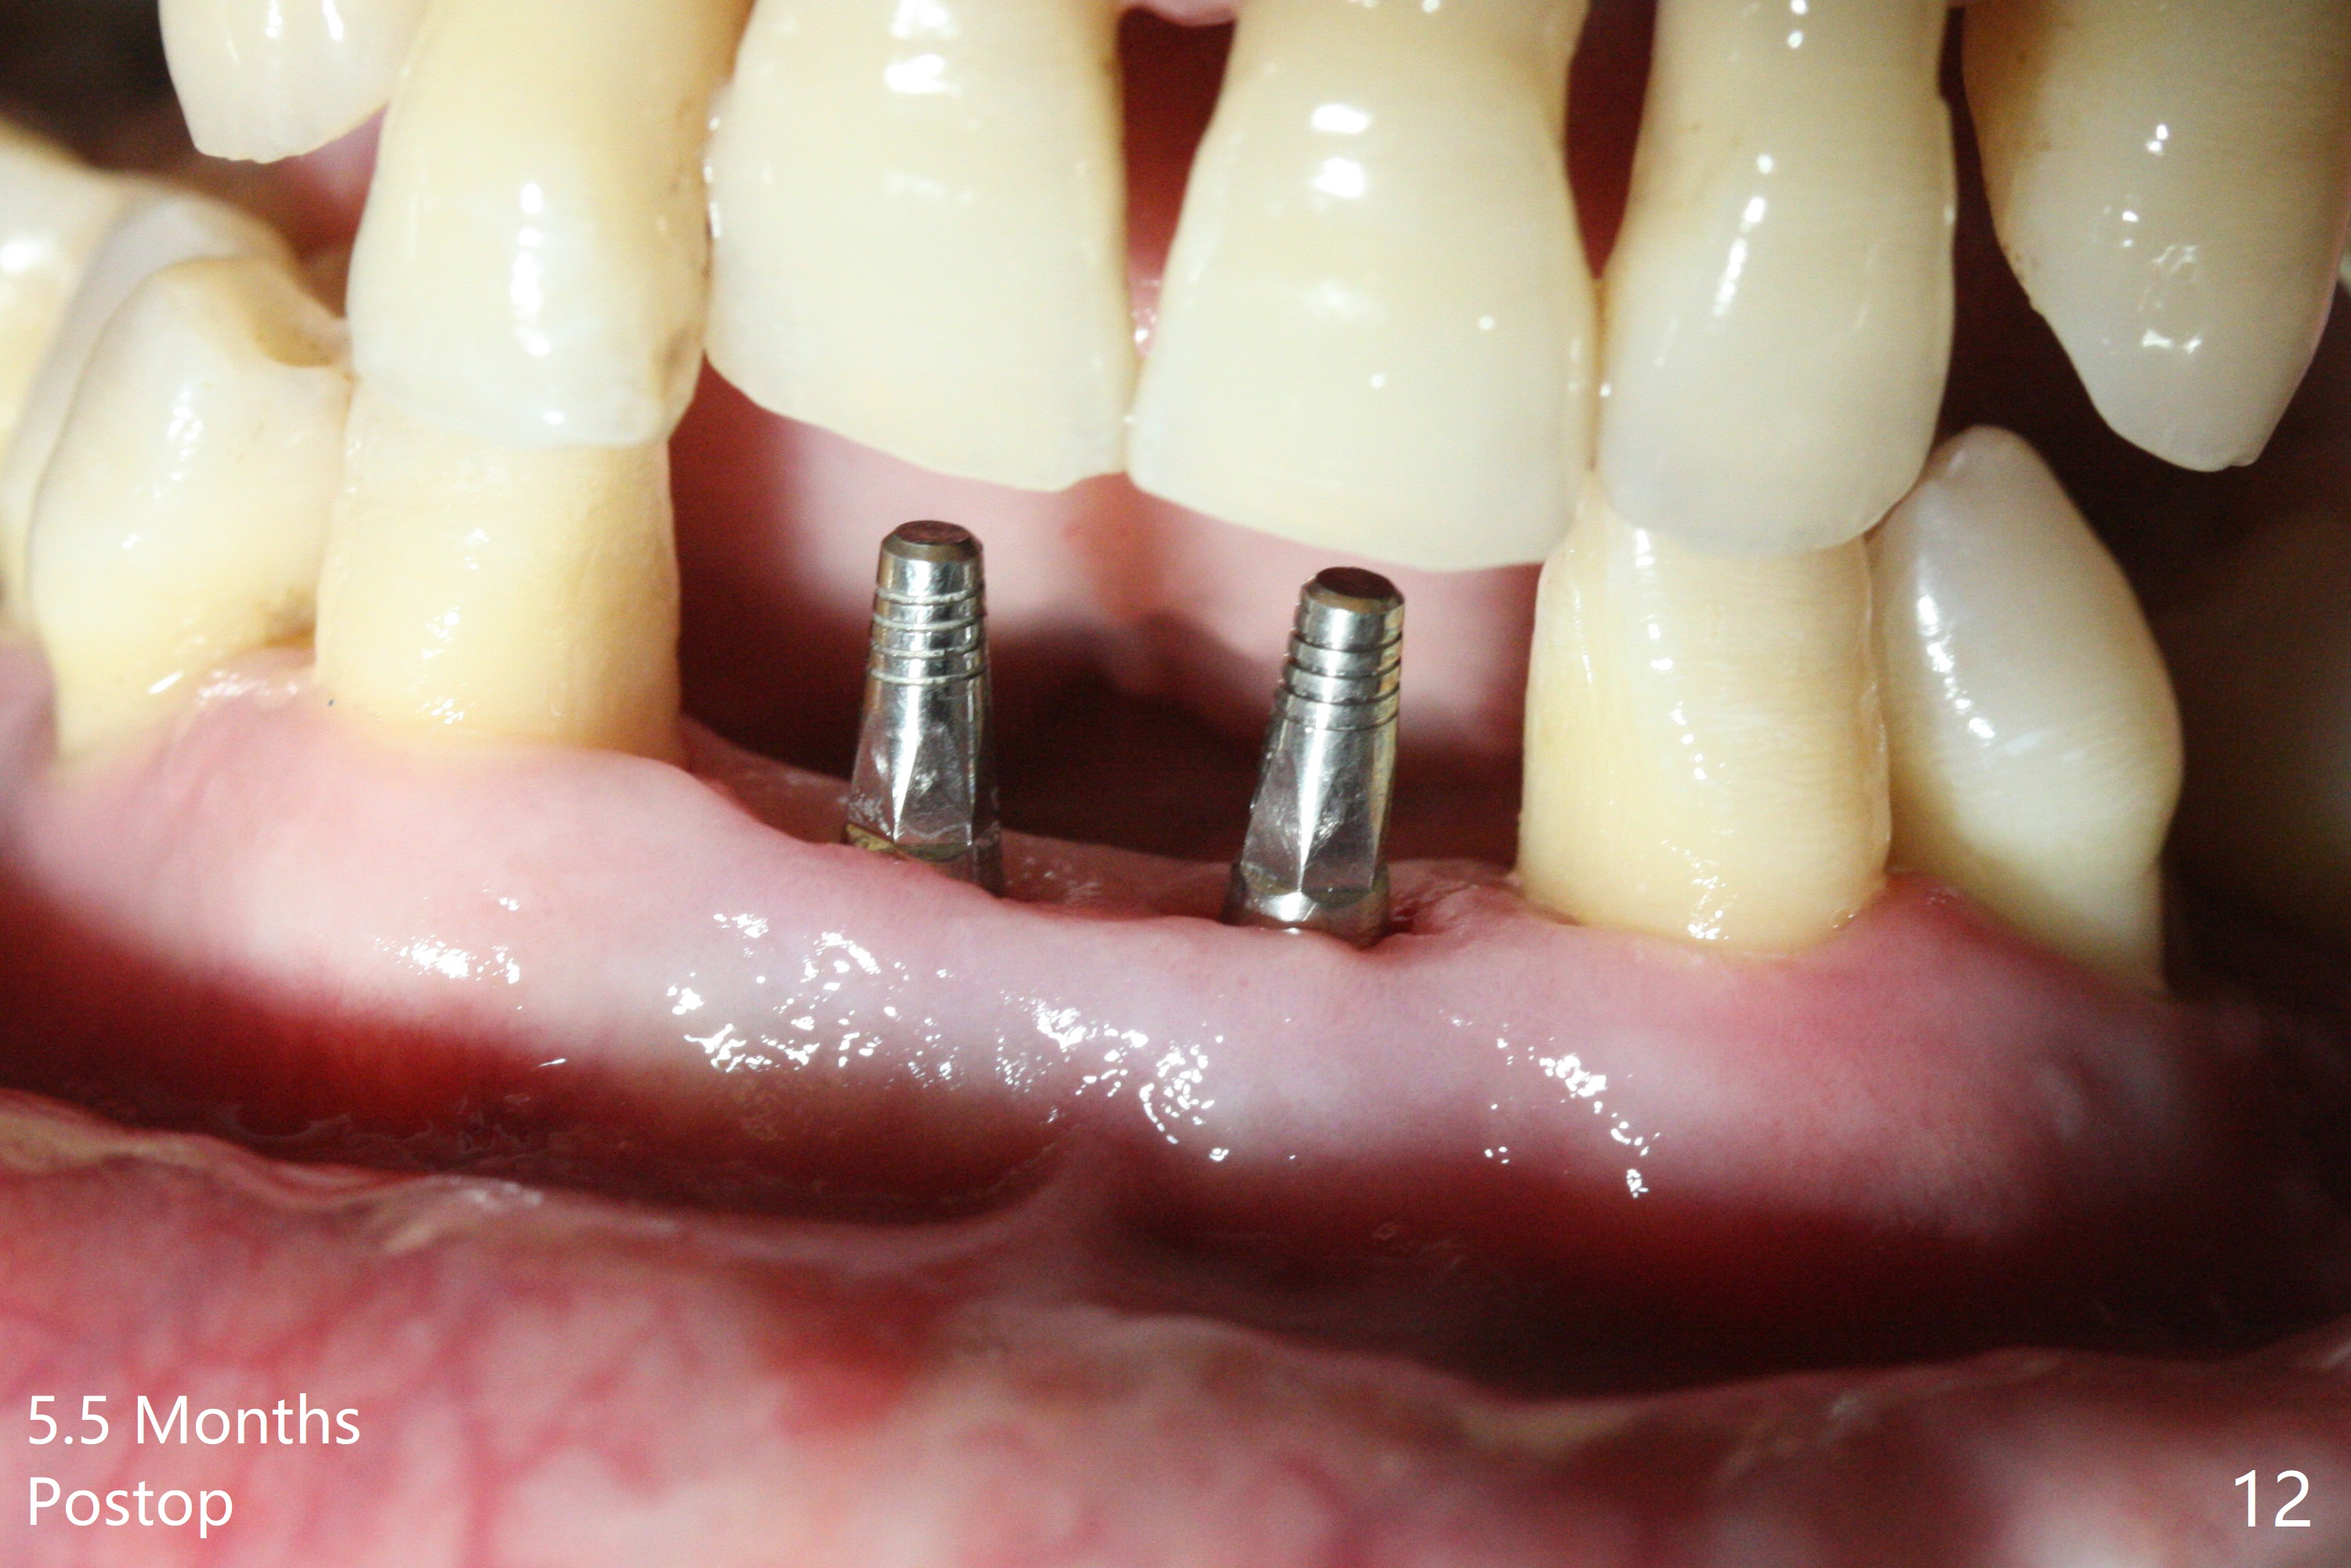

After extraction of 4 of the lower incisors, there are basically 2 sockets (#23/24 and 25/26), separated by the apparently midline bone (Fig.1 red line). In spite of using Lindamann bur to move the 25/26 osteotomy mesially, a 3x14(2) mm dummy implant remains close to the tooth #27 (Fig.2). The terminal branch of the Incisive Canal (<) is located between the lateral and central incisors. A de novo osteotomy (Fig.3 (1.5 mm drill)) is made mesial to the original one (O). While the 3x14(2) mm dummy implant is incompletely placed at #25/26, a 3x14(4) mm 1-piece one is placed at #23/24 (Fig.4). Finally the same implant is placed at #25/26 with placement of mineralized cortical/cancellous bone (Fig.5 *). When the large sockets are sutured, the supraerupted teeth #7-9 touch the lower gingiva (Fig.6). The incisal edge is reduced for clearance (Fig.7). Periodontal dressing is less likely to be dislodged with the incisal edge reduction (Fig.8,9). A provisional FPD is fabricated 1 week postop. Hard (Fig.10) and soft (Fig.11,12) tissues heal 5.5 months postop. The patient returns for crown cementation 3 months post impression (9 months postop, Fig.13,14).